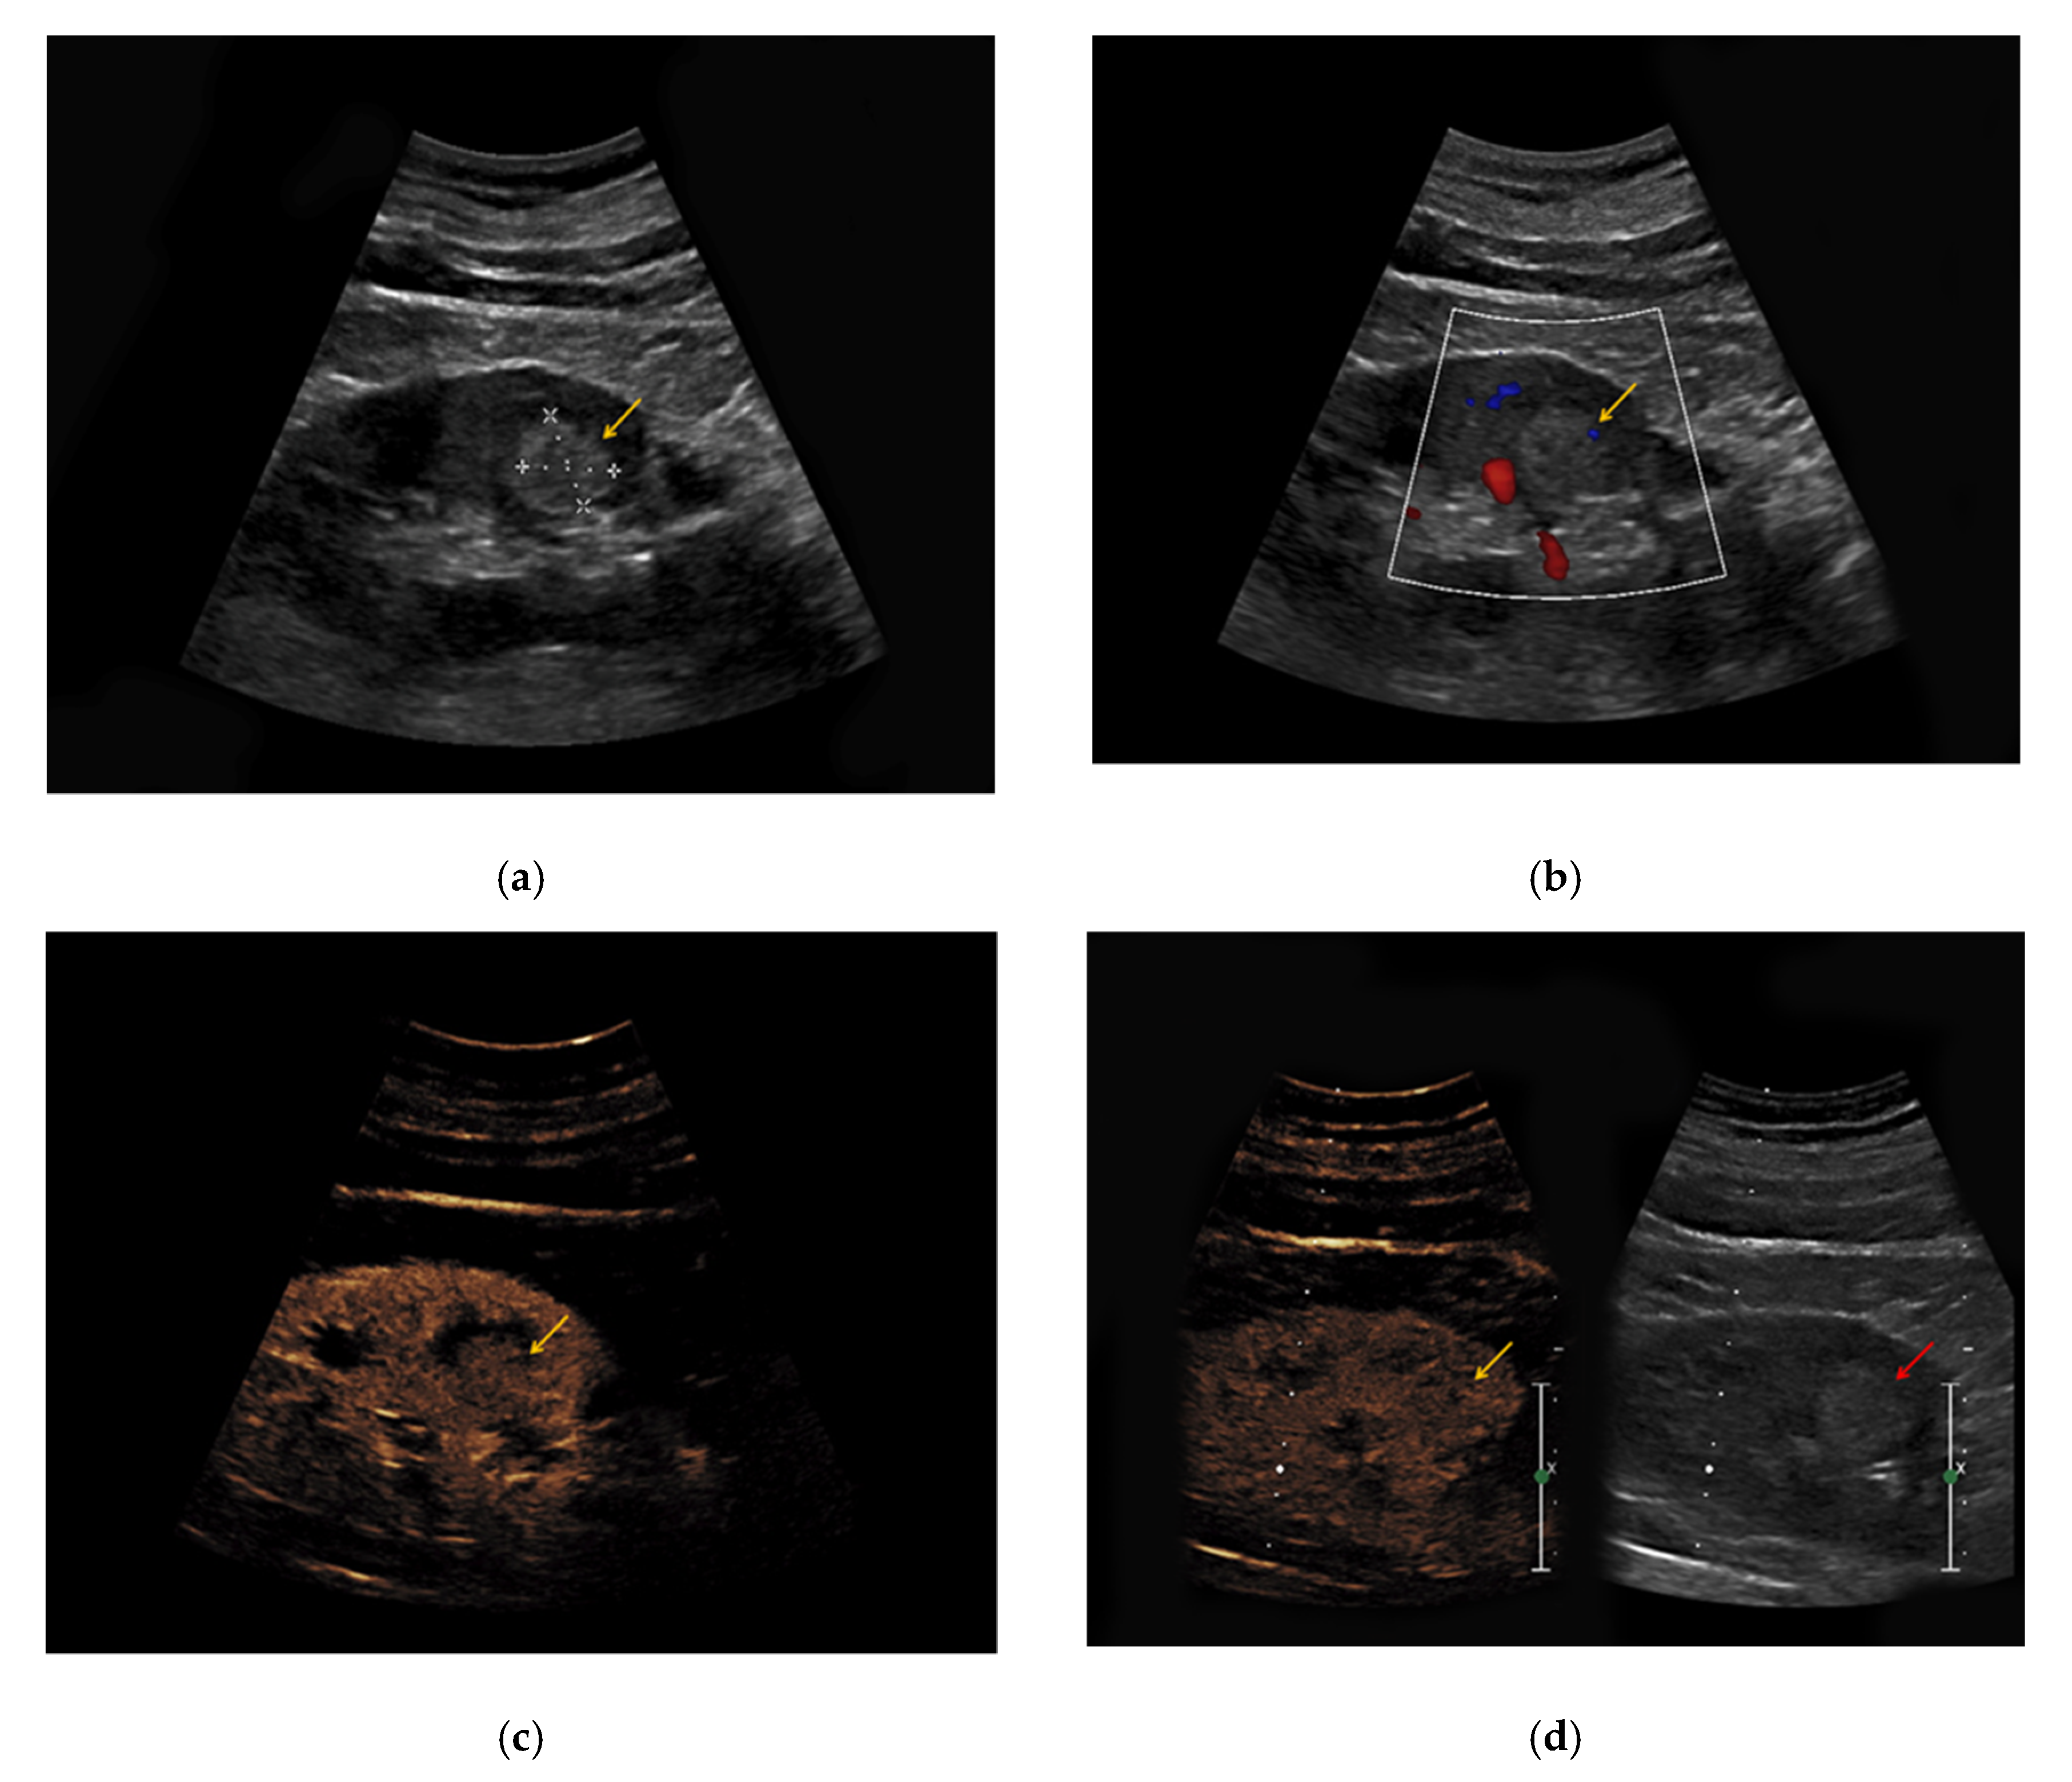

Figure 2. An 81-year-old patient with an unclear lesion in the right kidney incidentally detected in contrast-enhanced computed tomography (CT). (a) In native B-mode, an inhomogeneously hyperechoic lesion with a diameter of 2.5 cm could be registered (right picture, yellow arrow). In the corresponding contrast-enhanced CT scan (a, left picture, yellow arrow), the lesion presents hypodense with only low contrast-enhancement; (b) no major vascularization could be visualized in Doppler mode (right picture, red arrow). (c) CEUS shows a rapid hyperenhancement of the lesion (right picture, red arrow); (d) no wash-out in the late phase was registered (right picture, red arrow). The patient underwent partial nephrectomy, the results of the histopathological analysis revealed benign renal angiomyolipoma.

In 4/7 patients with confirmed angiomyolipoma, the lesions presented as hypoechoic in native B-mode (57%) and in 3/7 patients as hyperechoic (43%). Only one lesion showed slight hypervascularization in Doppler mode (14%). All lesions showed rapid contrast-enhancement (100%) (Figure 2), whereas only two lesions also showed venous wash-out (29%).